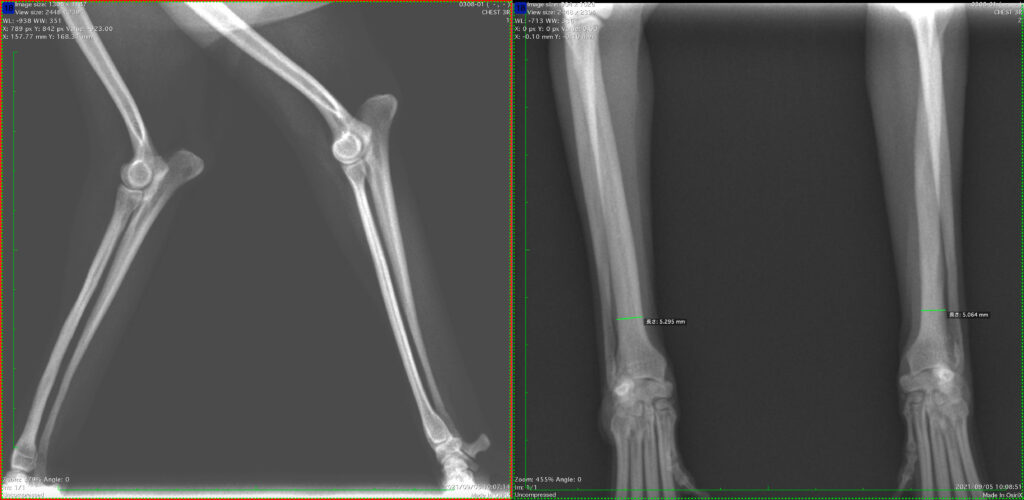

1. 骨折手術直後(ロッキングプレートとスクリューをして骨と固定しています)

きれいに骨折している面があっています。

2. 骨折手術2週間後

だいぶ骨がくっついてきました。

3. 骨折手術1ヶ月後

これで癒合はほとんど終了です

4. スクリューを抜いていきます

次は、このままではプレートによるストレスシールディング(骨が薄くなってくる骨粗鬆症のようなもの)が起きて、骨が脆くなっていってしまうので、プレートとスクリューを抜いていきます。

いきなり、全てを抜いてしまうと骨もびっくりして、再骨折してしまう可能性があるので、まずはスクリューを2本抜きます。

5. 残りのスクリューとプレートも抜きます

スクリューを抜いたところがレントゲンで黒く抜けているのがわかります。

これが白くなってきたら、残りのスクリューとプレートも抜きます

6. 終了

大丈夫そうなので、プレートとスクリューを抜きました。

これで骨折の手術は終了です。